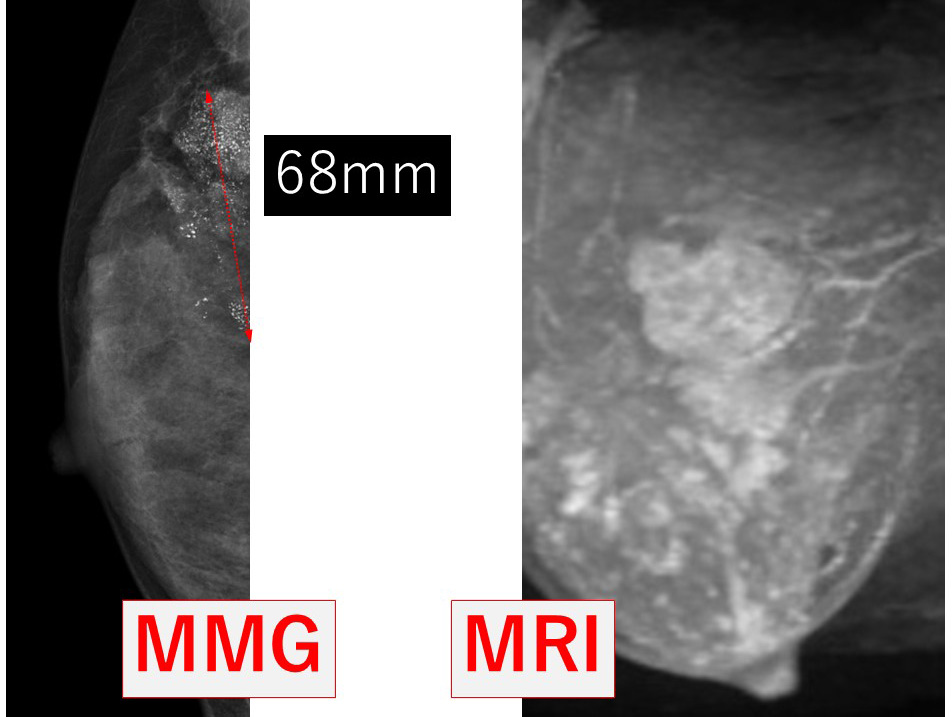

MRIでみると、このようになります。

7cm? この大きさで温存、無理やろ?

「整容性」保てないんじゃ?

そう思うのも無理はない。

実際に、医療機関によっては「7cm ! 温存? 無理無理」と相手にされないかもしれない。

左 正面像(MRI) 右 側面像(MRI)